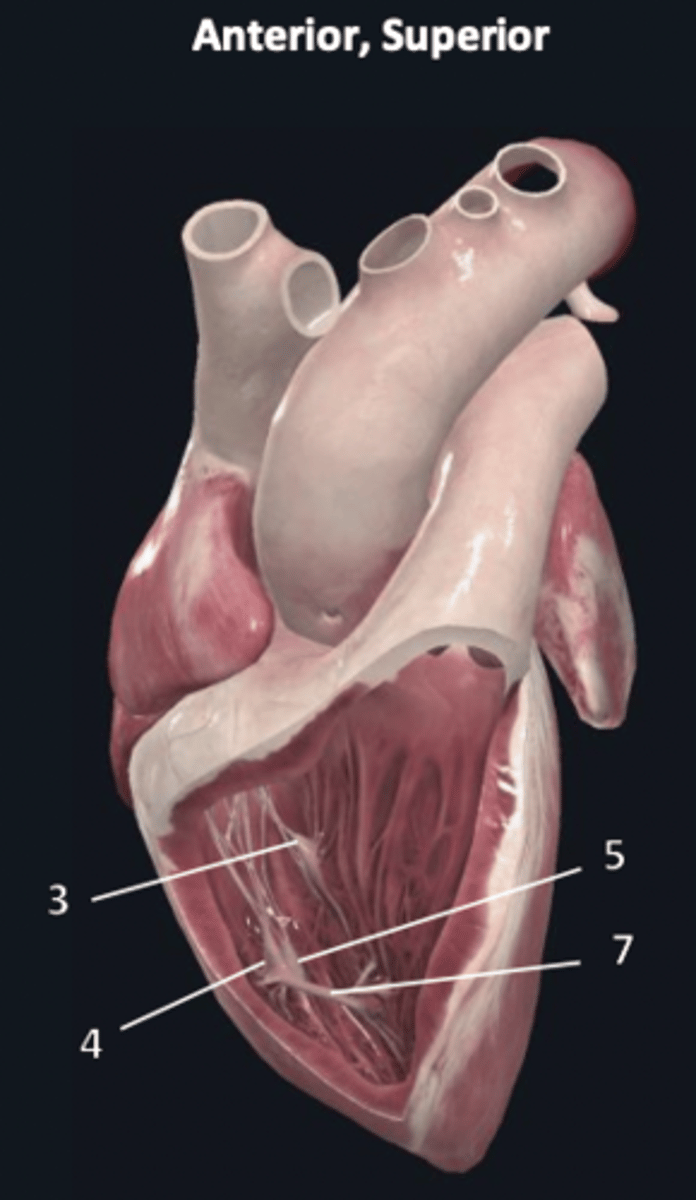

left atrium

1

left auricle

2

left ventricle

3

trabeculae carneae

4

inferior papillary muscle

5

superior papillary muscle

6

chordae tendineae

7

left atrioventricular valve

8 (opening)

aortic semilunar valve

9 (opening)